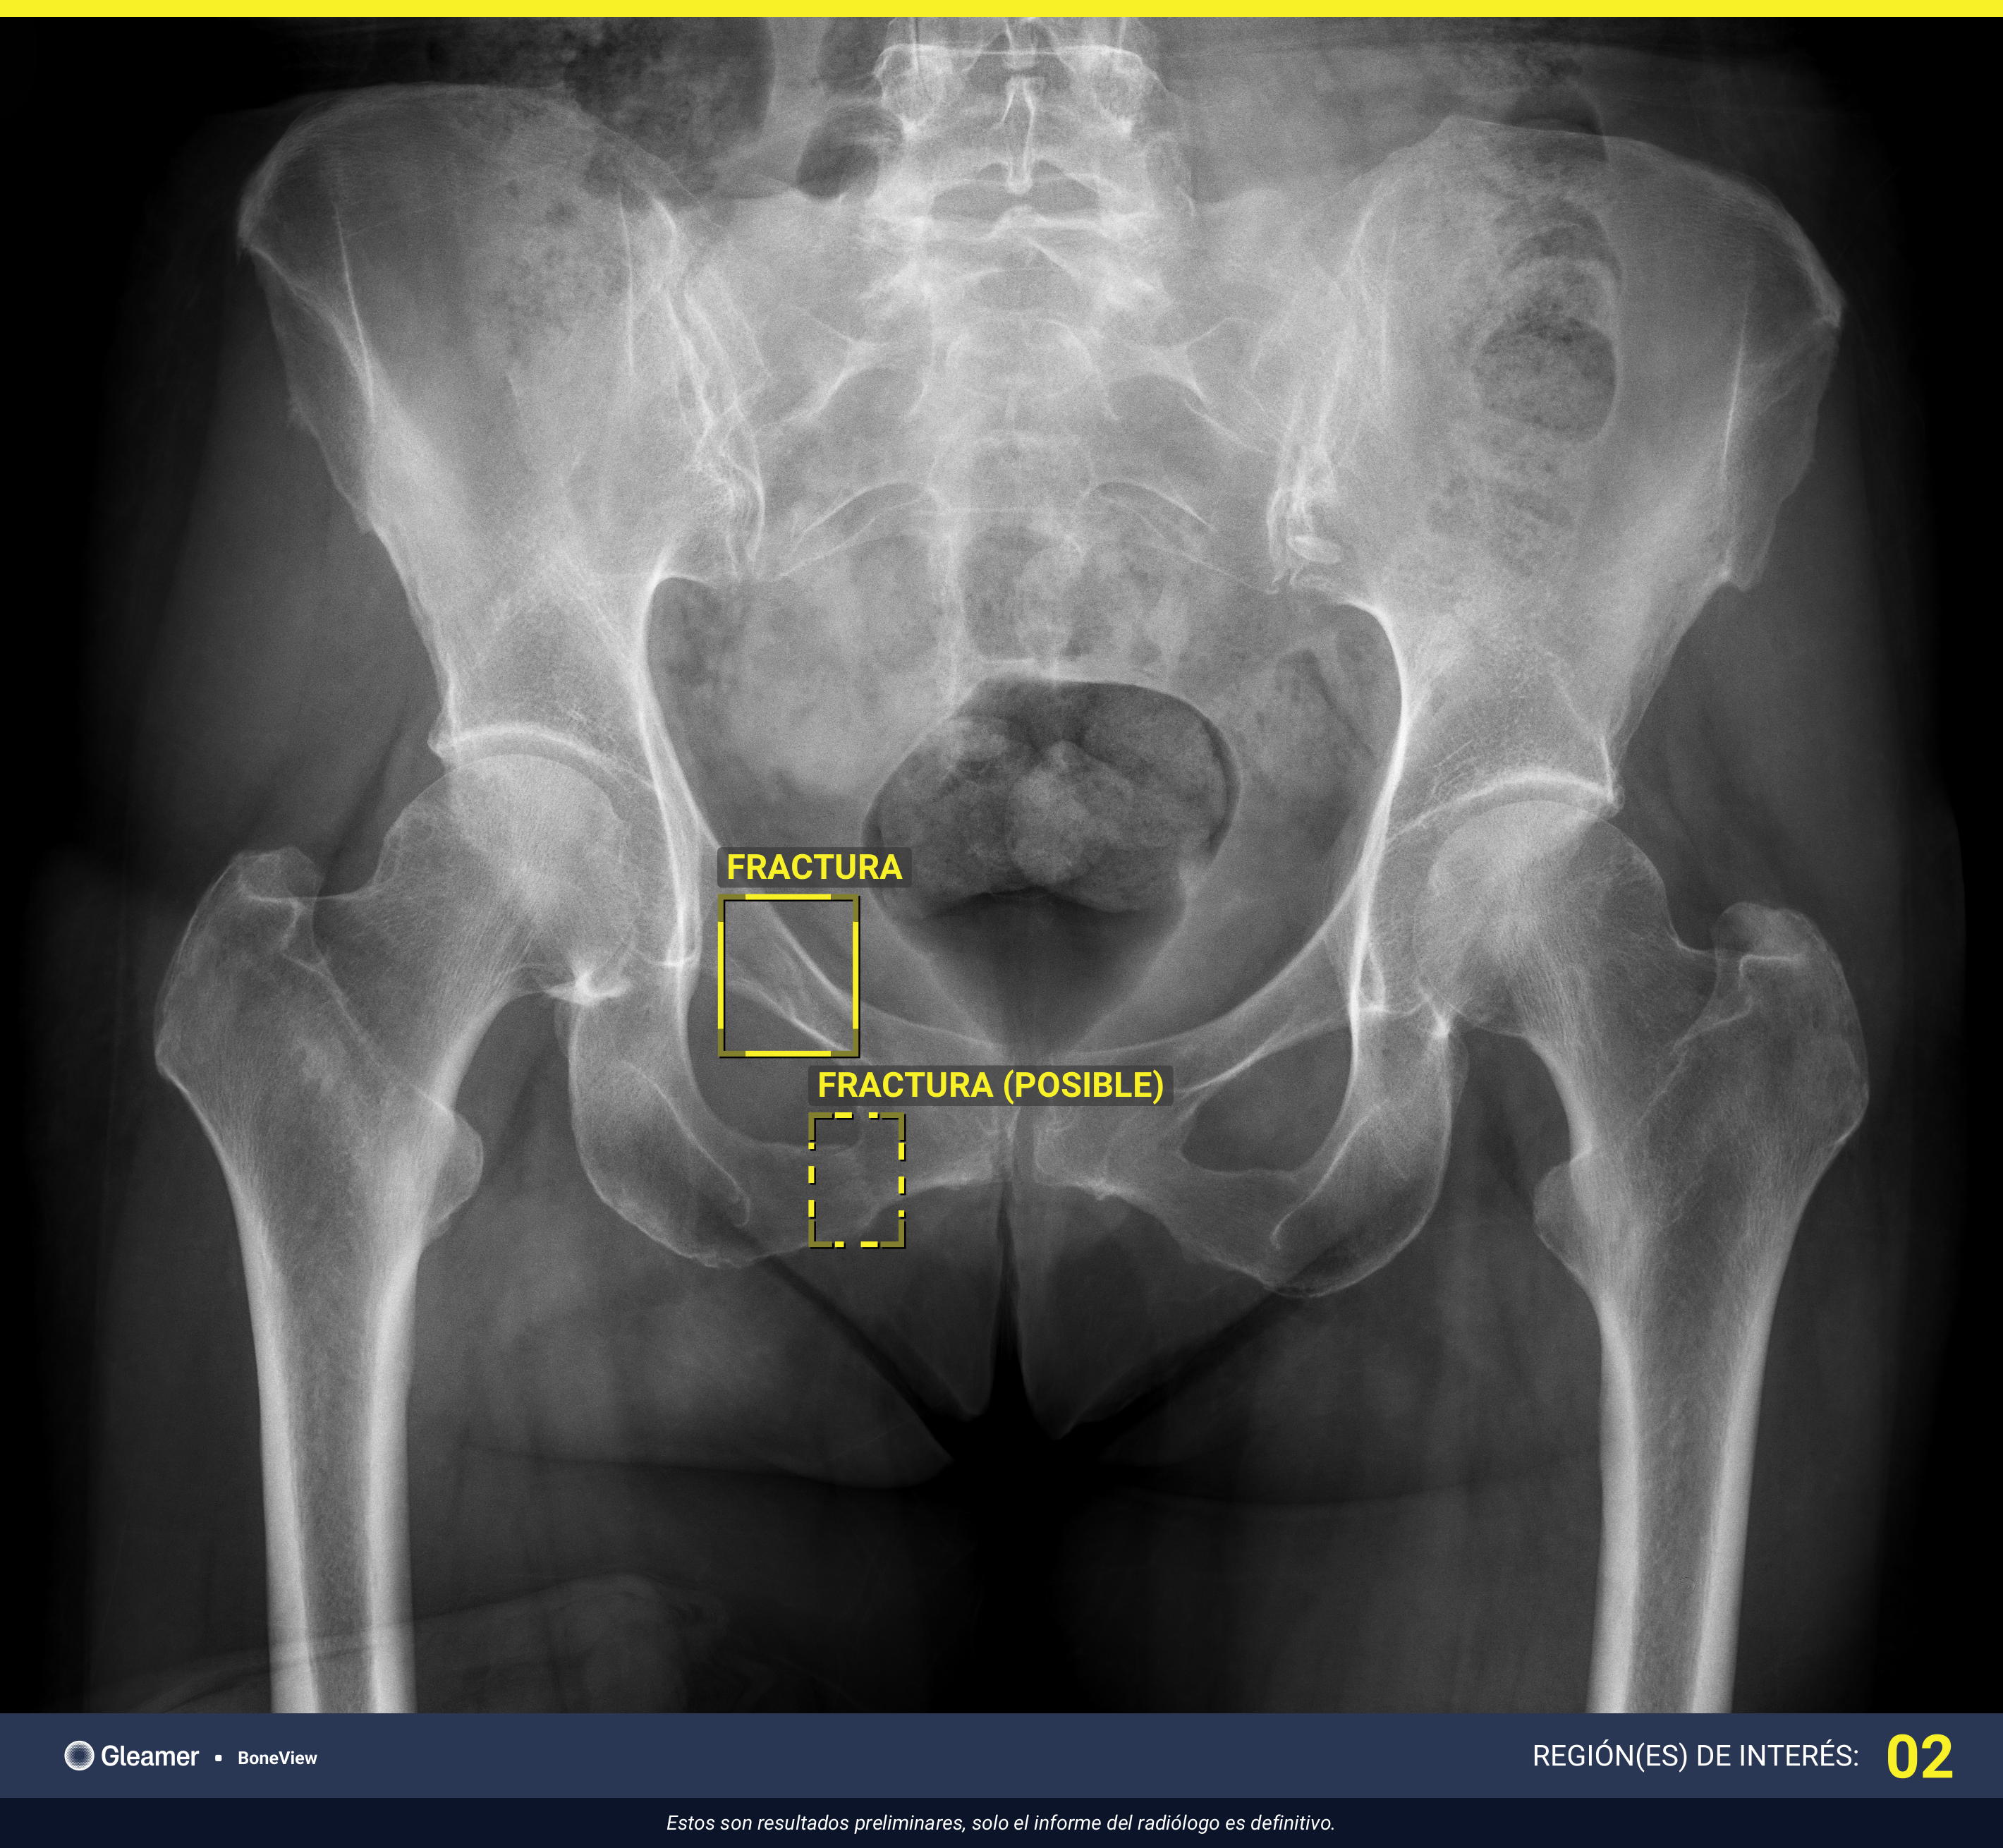

902 POSITIVE